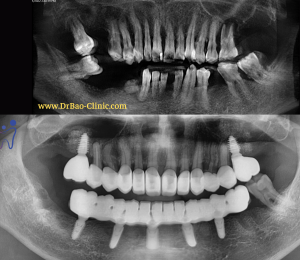

Anh khách hàng nam (40 tuổi) đến nha khoa thăm khám và mong muốn cải thiện sức nhai và thẩm mỹ.

Qua thăm khám lâm sàng lần đầu, thực sự chúng tôi cũng chưa biết phải bắt đầu điều trị từ đâu và quá trình điều trị ra sao.

– Răng của anh đã được bọc sứ toàn bộ cả 2 hàm, trừ 2 răng cối nhỏ.

– Nướu luôn viêm đỏ, chảy máu.

– Răng ê buốt ngay cả với nước bình thường.

– Khớp cắn thì hở toàn bộ vùng răng cửa, vùng răng sau thì cắn ngược và không ổn định – không có một vị trí lồng múi cố định.

– Điều trị viêm nha chu.

– Tháo toàn bộ răng sứ cũ.

– Nhổ răng nhiễm trùng nặng.

– Thiết kế lại phục hình toàn miệng bằng răng tạm PMMA rồi sau đó cấy implant theo thiết kế phục hình.

– Kết hợp ghép xương và ghép nướu tạo độ ổn định cho phục hình trên implant sau này.

– Thiết kế, điều chỉnh răng tạm PMMA nhiều lần để đạt được khớp cắn ổn định và thoải mái nhất.